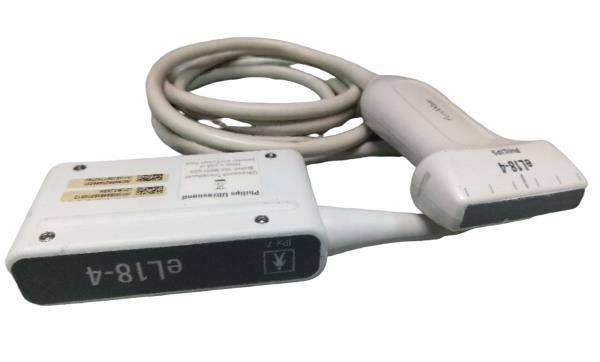

The system typically comes with a probe that is specifically designed to provide clear imaging of the animal’s reproductive organs, allowing the veterinarian to determine the pregnancy status, number of fetuses, and their development stages. With real-time imaging and high-resolution capabilities, it helps in assessing the health of the fetus and identifying potential complications. The machine is lightweight and portable, making it easy to use on farms or in field environments. This ultrasound system is a valuable tool for ensuring the health and wellbeing of pregnant animals and managing breeding programs efficiently.